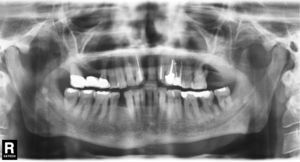

Si la causa de estos cuadros es bacteriana, se pueden formar abscesos crípticos en el tejido linfático de las amígdalas o del anillo faríngeo de Waldeyer. En determinadas circunstancias curan dejando una cicatriz, lo que a la larga favorece la aparición de calcificaciones. Es muy frecuente que estas alteraciones se proyecten en las radiografías panorámicas sobre la rama mandibular (fig. 1). Es posible que, en función del momento en que se obtuvo la radiografía panorámica, hayan pasado varios años o incluso décadas desde que se produjo la enfermedad causal.